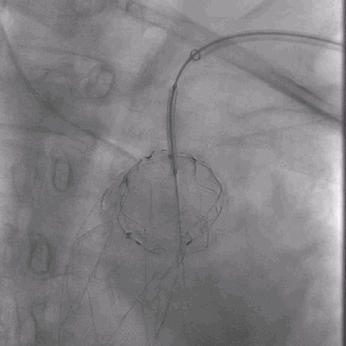

03. 左侧肱动脉采用0.018"导丝配合0.035"支撑导管顺利破膜,先后引入4*30mm球囊、7*80mm球囊、MUSTANG 8*40mm球囊扩张开窗口。

0.018"导丝配合0.035"支撑导管顺利破膜

RAO确认破膜成功并置入4*30m球囊